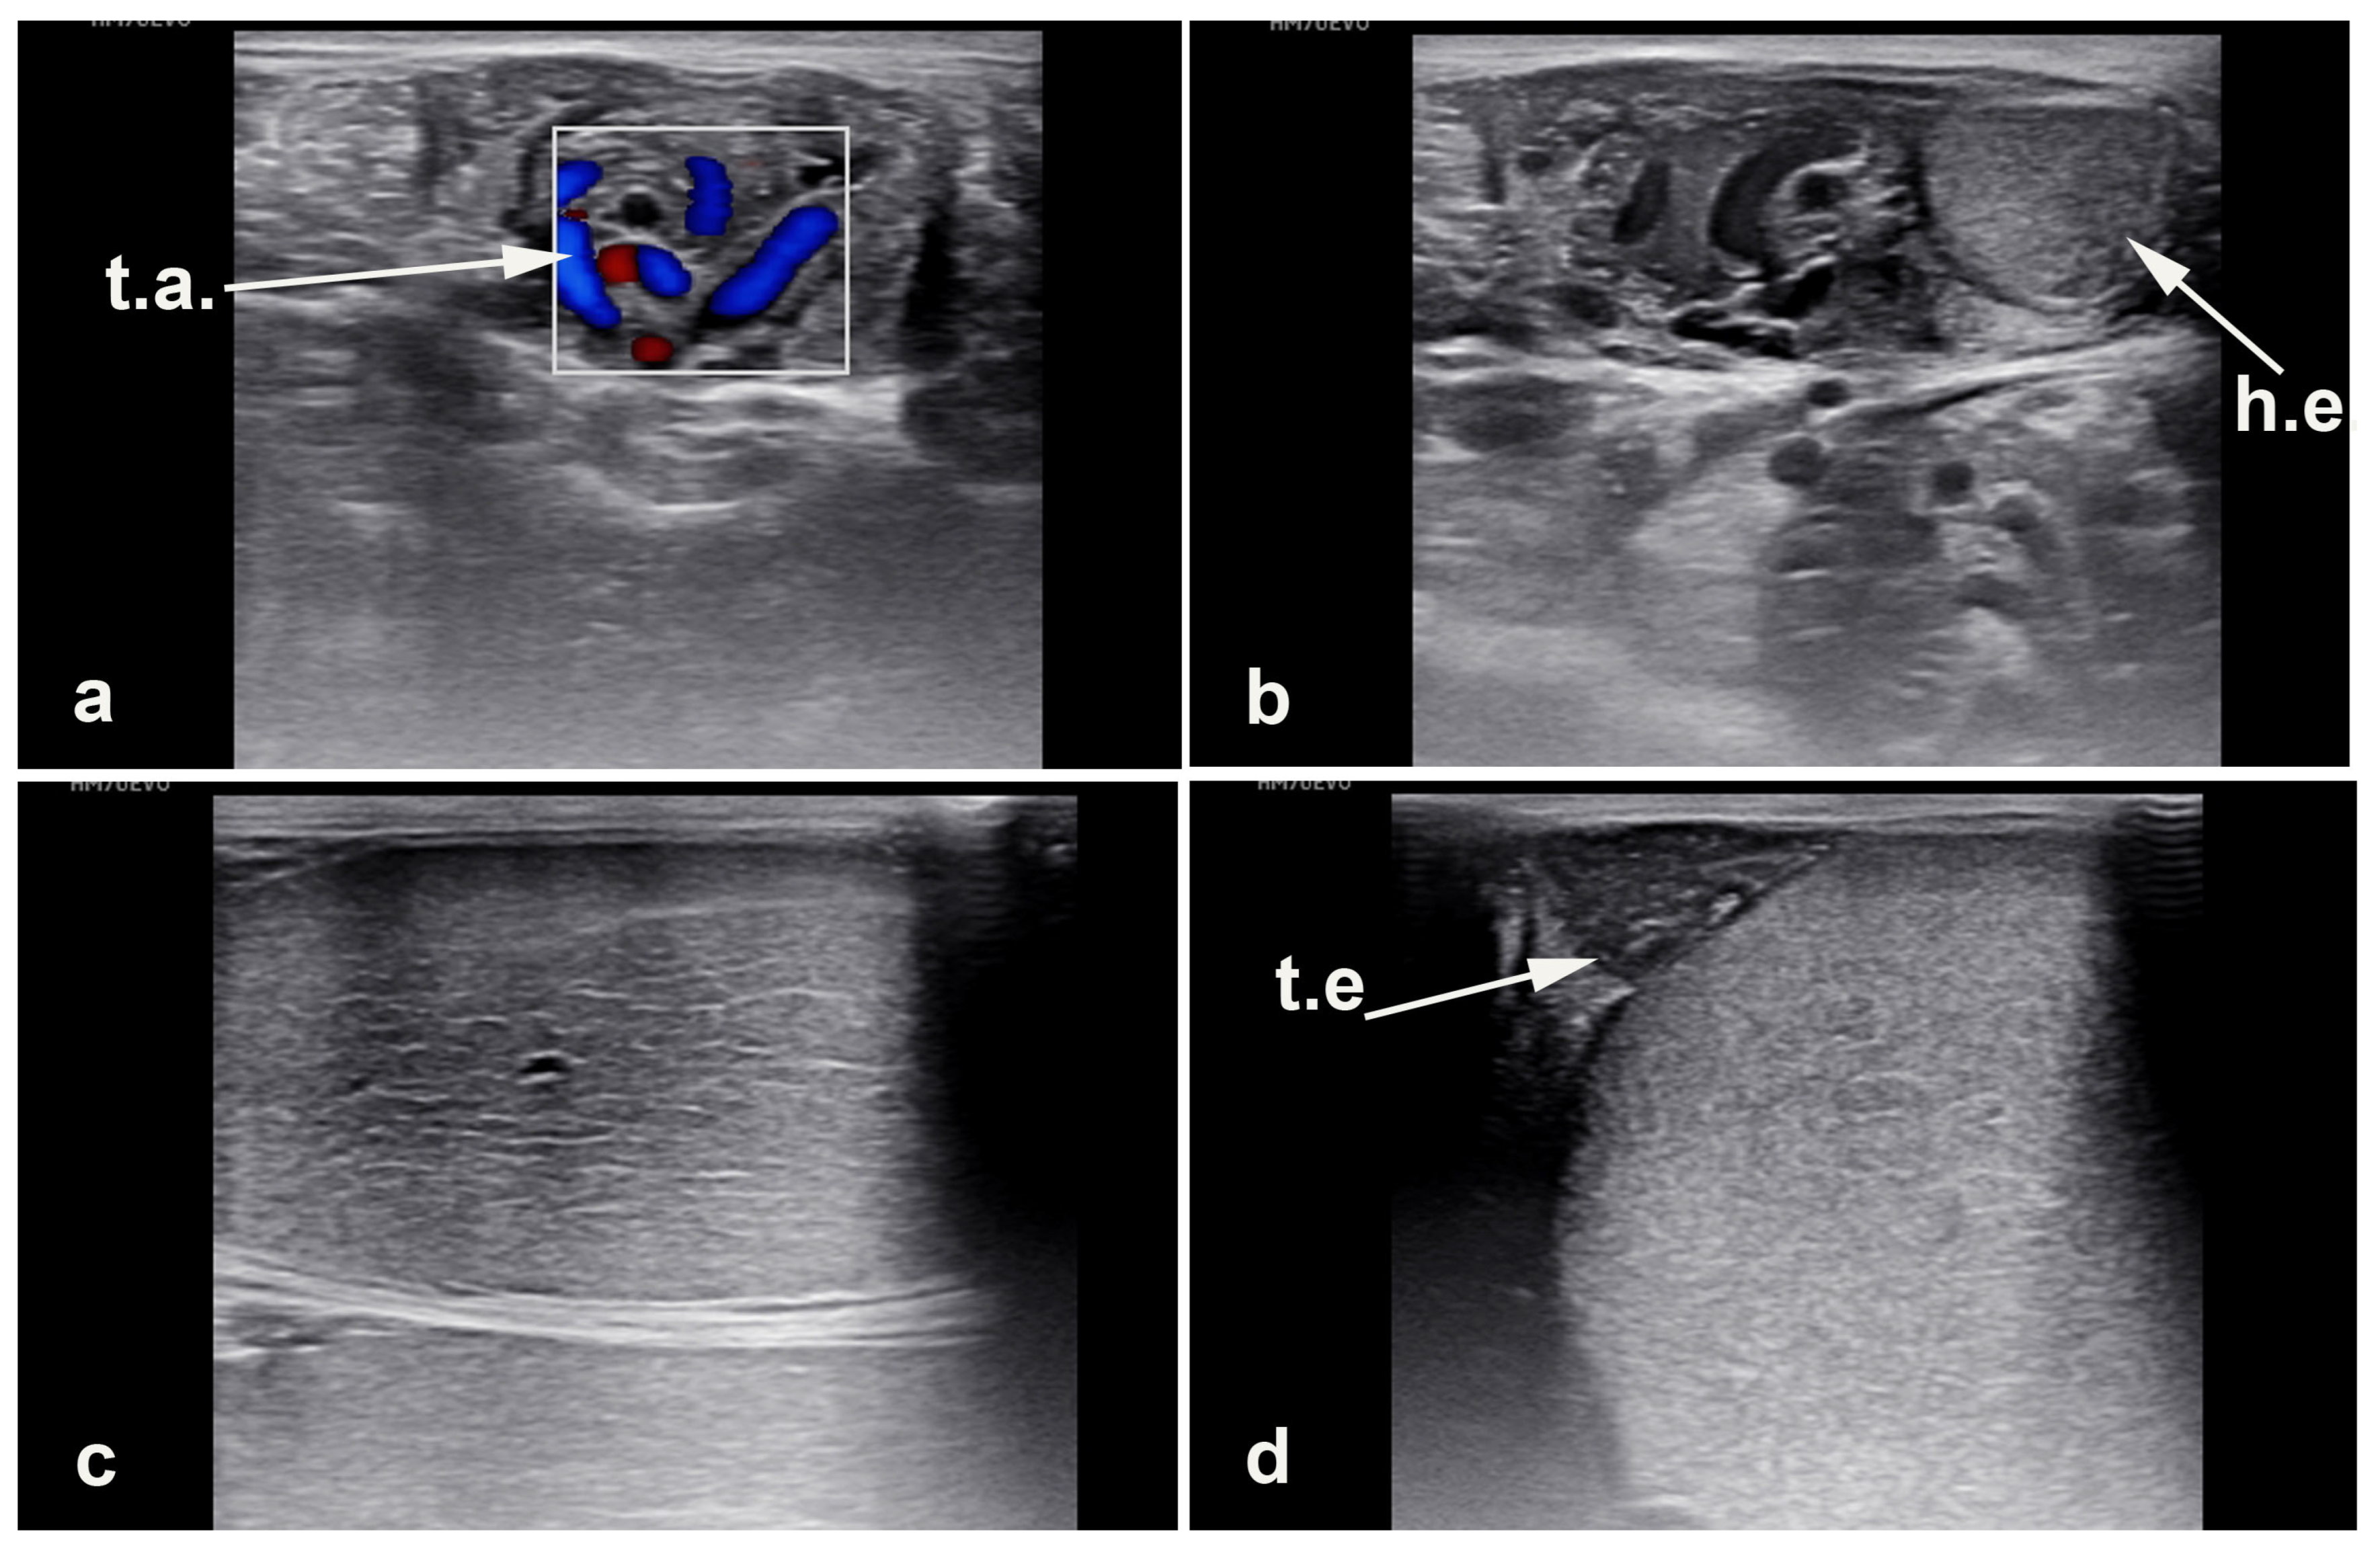

4.2. Acquired Scrotal/Inguinal Hernia

4.3. Torsion of the Spermatic Cord